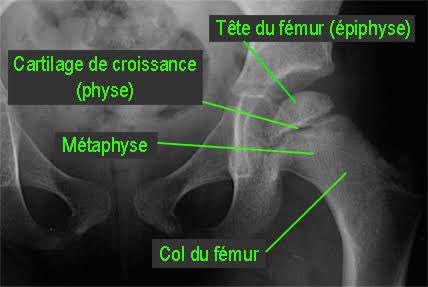

Mais celle d& #39;un enfant... comme on peut le voir ici (fléchés) car les cartilages de croissance des fémurs ne sont pas soudés (le trait noir entre l& #39;epiphyse et la métaphyse) contrairement à une hanche adulte.